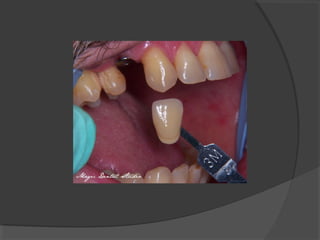

c) Class III Cavities:

These cavities occur in the proximal surfaces

(mesial and distal) of incisors and canines; but do

not involve or include the incisal angle.

d) Class IV Cavities:

Cavities that originate on the mesial and distal

surfaces of incisor and canine teeth, but caries is so

extensive that the incisal angle is involved.